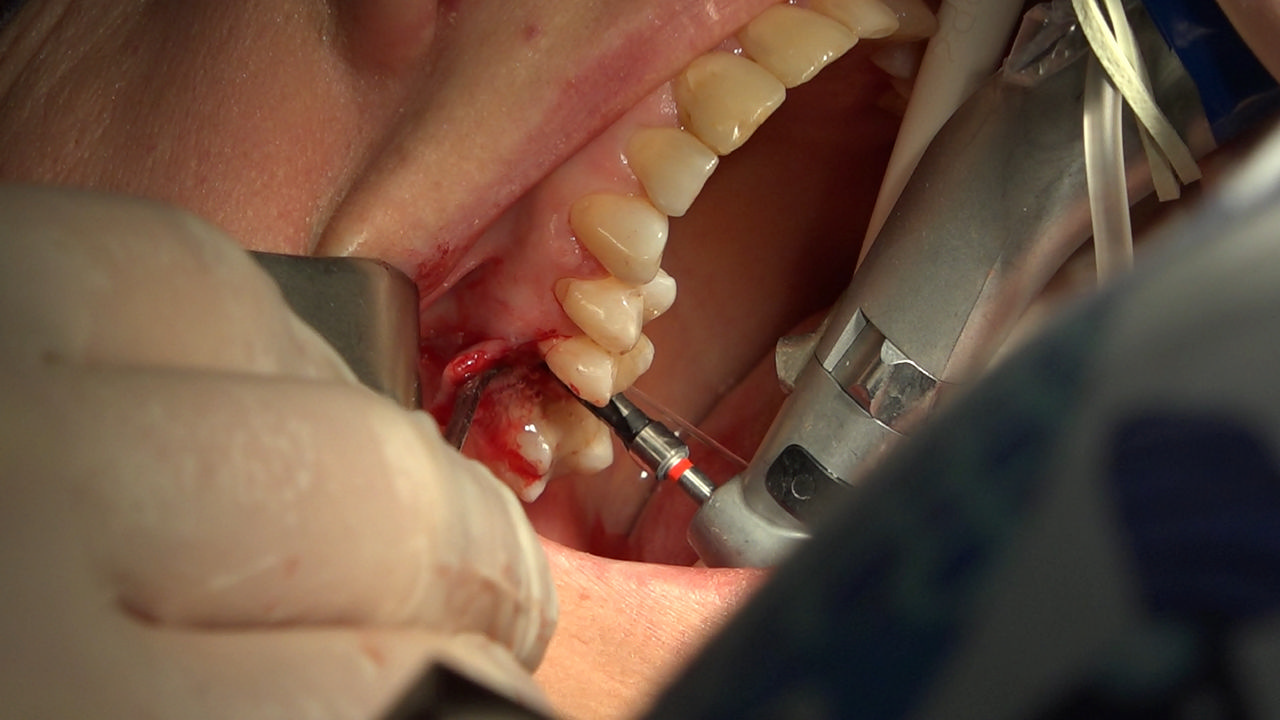

7 Sesja X Sezonu Practiculum Implantologii, w której brali udział kursanci z Grupy A i B, obejmowała implantacje wykonane systemem Axiom, procedury regeneracyjne tkanki kostnej i zabieg sinus lift oraz procedury implantoptotetyczne. Ten zakres szkolenia poprowadziła dr Małgorzata Piotrowska. Protetyka na implantach, to finalny etap leczenia implantologicznego decydujący o uzyskaniu harmonijnego łuku zębowego, okluzji oraz szczelności połączeń, a więc zadowoleniu Pacjenta i powodzeniu całego procesu leczenia.

Jego sednem jest wybór optymalnego rozwiązania rekonstrukcji protetycznej uwzględniający bardzo wiele czynników o charakterze mechanicznym, funkcjonalnym i estetycznym, związanych ze stanem tkanki kostnej, jamy ustnej i uzębienia. Odbywa się już na etapie tomografii komputerowej i jest ściśle powiązany z częścią chirurgiczną, ponieważ prawidłowe zaplanowanie pracy i usytuowania implantów wspomagane plastyką tkanek miękkich, to dla procedur protetycznych baza wyjściowa. Zasady te są jak najbardziej oczywiste, zarówno przy samodzielnym wykonywaniu leczenia implantologicznego, jak i przy podziale zadań dla chirurga i protetyka, czyli pracy w duecie.